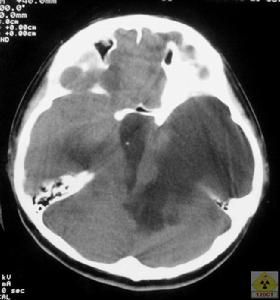

腦CT3、CT和MRI。是診斷腦積水的主要和可靠方法。有助於明確病因、分類和區別其它原因引起的腦室擴大,且可觀察分流術後腦室變化情況以追蹤分流術的效果。特別是核磁電影成像(Cine-MRI),在區別梗阻性和交通性腦積水上具有決定性作用,同時也能區別正常壓力腦積水及腦萎縮導致的腦室擴大。

1、CT:可以顯示腦室的大小、皮層萎縮的程度及相關的病變。在正常壓力腦積水中,腦室明顯擴大,同時出現腦溝加深,但兩者不成比

例,而以腦室擴大更明顯。在有些病人,腦室周圍低密度是重要的表現。